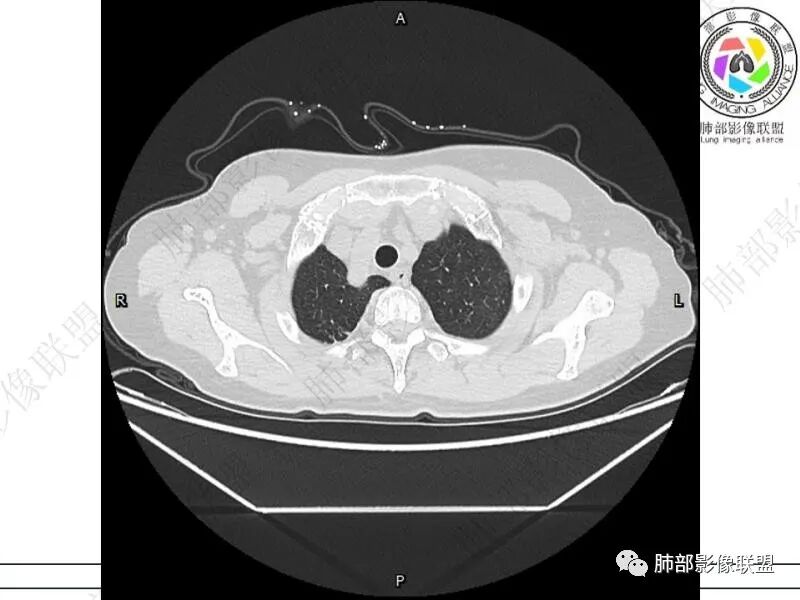

摘星空竹子:两肺胸膜下多发实性结节、磨玻璃影及实变影,短期复查病变有所进展,考虑感染性病变,隐球菌可能,患者有右半结肠癌手术史,转移不能除外。

简单:双肺及胸膜下多发小结节,双下肺胸膜下宽基底团块影,短期内病灶进展考虑炎性病变,隐球?患者ca术后,双肺小结节随诊除外转移

放射小白:老年女性,肠癌手术病史;影像表现,两肺胸膜下见微小结节及实变影,住院治疗后病情加重,两肺下叶胸膜下实变范围变大,首先考虑OP/COP,鉴别隐球菌,最后挂上淋巴瘤,感觉不像。

丽:双肺下叶胸膜下多发片状高密度影,边缘模糊不清,内可见支气管穿行,病变长轴平行于胸膜,考虑感染性病变,隐球菌

媛:肠癌术后,免疫力低下。两肺胸膜下结节及实变影,实变影长轴平行于胸膜,密度均匀,边界偏清,周围有晕征,短期复查进展,虽隐球菌荚膜抗原检测阴性,还是考虑隐球菌,鉴别OP

songml:老年女性,结肠癌术后,下腹隐痛。双肺胸膜下散在结节影,大小不一,下肺为著,肺野清晰,实变结节有强化,有毛毛征。考虑隐球菌感染。

谢加平:结肠癌术后史,两肺胸膜下多发结节及斑块实变病灶,实边边界平直征(亚急性和慢性病变过程),双肺下叶后基底段胸膜下为甚,与胸膜平行特点,见支气管充气征,边缘模糊的GG0,首诊2022年11月18日肺部CT,与治疗11月28日对比,病灶未吸收,双肺下叶胸膜下病灶有侧向融合特点,综合分析符合炎性肉芽肿,隐球菌感染。

良孑:两肺胸膜下多发相类似结节,部分结节有晕及晕中软毛刺,部分结节侧向融合,长轴与胸膜平行,结节边缘可见刀切征,右半结肠癌术后免疫力低下,综合考虑支持隐球菌

老年女性,结肠癌术后。两下肺胸膜下为主片状实变,右下肺短期复查融合且病灶长轴平行于胸膜,实变内可见支气管充气征,边缘磨玻璃晕,另两肺内胸膜下散在数枚小结节状、楔形实性灶。考虑感染性病变,隐球菌可能,鉴别肺转移。

2.影像特征:双肺胸膜下多发实性结节、磨玻璃影及实变影,胸膜下优势分布、晕征、胸膜下脂肪间隙存在,部分病灶边界平直征,有侧向融合趋势。